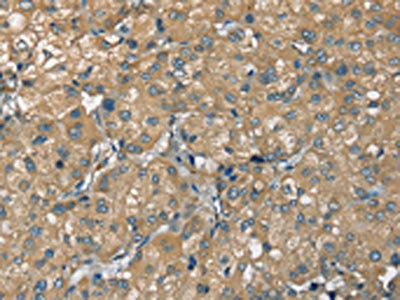

The image on the left is immunohistochemistry of paraffin-embedded Human thyroid cancer tissue using CSB-PA985822(ATP2A3 Antibody) at dilution 1/30, on the right is treated with synthetic peptide. (Original magnification: ×200)

The image on the left is immunohistochemistry of paraffin-embedded Human liver cancer tissue using CSB-PA985822(ATP2A3 Antibody) at dilution 1/30, on the right is treated with synthetic peptide. (Original magnification: ×200)